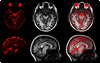

Single-shot Echo Planar Imaging (EPI) is one of the most efficient magnetic resonance imaging (MRI) acquisition schemes, producing relatively high-definition images in 100 ms or less. These qualities make it desirable for Diffusion Tensor Imaging (DTI), functional MRI (fMRI), and Dynamic Susceptibility Contrast MRI (DSC-MRI). However, EPI suffers from severe spatial and intensity distortion due to B(0) field inhomogeneity induced by magnetic susceptibility variations. Anatomically accurate, undistorted images are essential for relating DTI and fMRI images with anatomical MRI scans, and for spatial registration with other modalities. We present here a fast, robust, and accurate procedure for correcting EPI images from such spatial and intensity distortions. The method involves acquisition of scans with opposite phase encoding polarities, resulting in opposite spatial distortion patterns, and alignment of the resulting images using a fast nonlinear registration procedure. We show that this method, requiring minimal additional scan time, provides superior accuracy relative to the more commonly used, and more time consuming, field mapping approach. This method is also highly computationally efficient, allowing for direct "real-time" implementation on the MRI scanner. We further demonstrate that the proposed method can be used to recover dropouts in gradient echo (BOLD and DSC-MRI) EPI images.